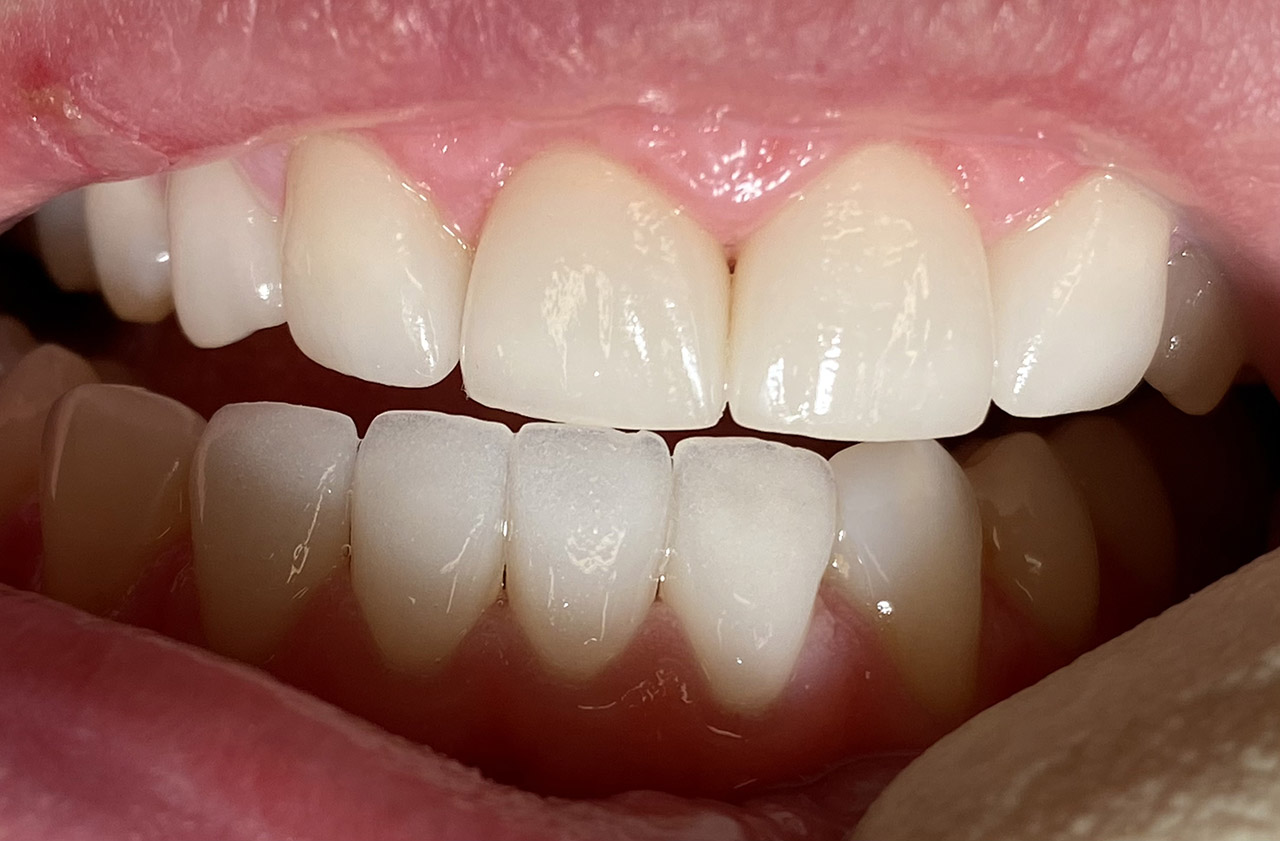

Internes und Externes Bleaching (Bleichen):

Nach Unfall mit E-Scooter unbefriedigendes Ergebnis der Erstversorgung (alio loco). Therapievorschlag: Stiftzähne?

Unsere minimalinvasive Therapie: Revision der Wurzelbehandlungen, danach internes und externes Bleaching, adhäsive Kunststoffüllungen in Schichttechnik. (Titel meiner Diplomarbeit 2003 “Die Vermeidung von Extraktion und Wurzelspitzenresektion durch zeitgemässe Endodontie in der Privatpraxis”)